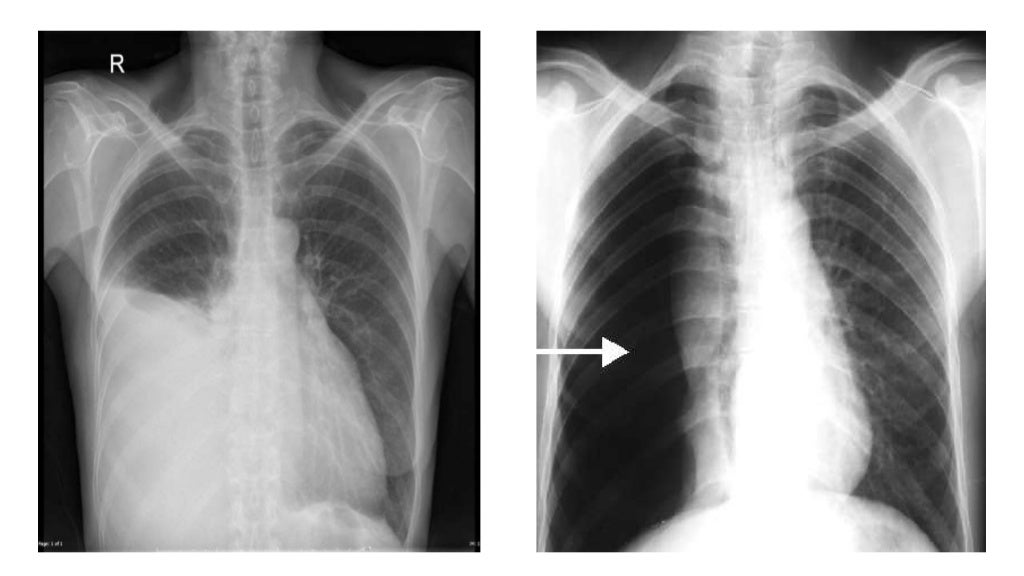

Radiographie du thorax vue de face Radio Thorax Slideshare Radiological anatomy of thorax dr. Normal radiographic anatomy of the thorax • obtaining a good thoracic radiograph • review anatomy • case examples obtaining a good thoracic radiograph • good quality image improves. Radiological anatomy of the chest. The chest methods of examination. Vohra pleura is a double layered membrane that invests both lungs, lies on either side of the. Radio Thorax Slideshare.